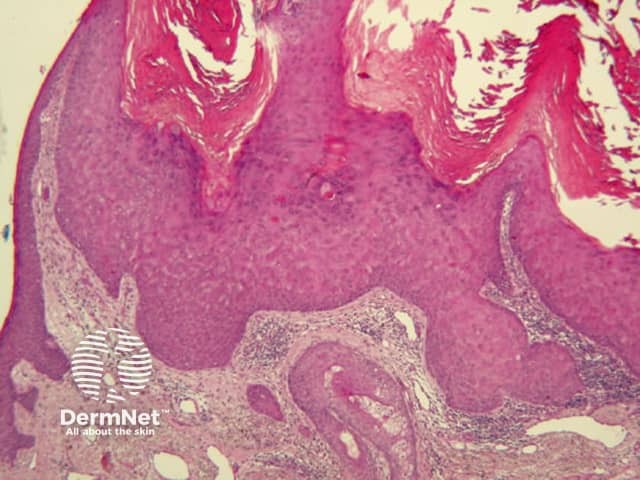

Seborrhoeic keratoses are amongst the most variable lesions on dermatoscopy, which is reflected in their protean histological appearances (Figure 15). Aside from the pseudopod pattern, any pattern or colour can be found. Flat seborrhoeic keratoses appear similar to solar lentigo on dermatoscopy. With early epidermal acanthosis thin curved lines (Figure 13) and circles become manifest, whilst with advanced acanthosis thick curved lines (Figure 14) and clods typically predominate. White clods are due to keratin under the stratum corneum. Orthokeratotic loosely laminated surface keratin appears yellow. Crypts fill with discoloured keratin and may appear various colours on dermatoscopy including brown and orange (Figure 15).

Figure 13 Figure 14 Figure 15

Figure 15a Figure 15b Figure 15c